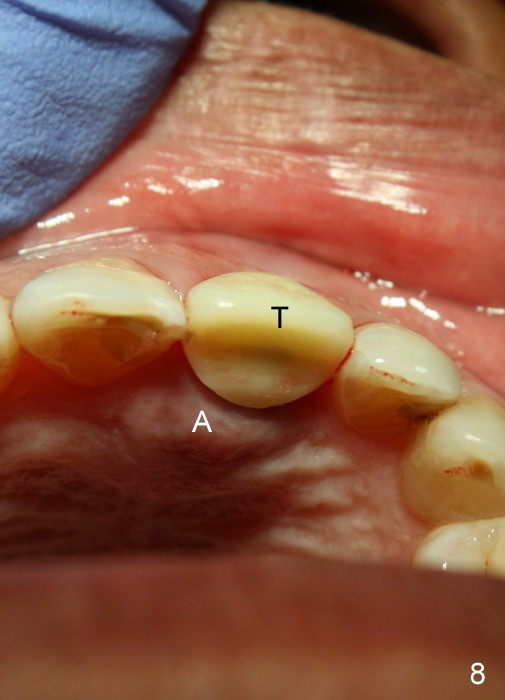

A 65-year-old man had injury to the tooth #9 20 years ago. The tooth has been discolored since (Fig.1). The tooth remained asymptomatic until last year. It has been loose since then. X-ray shows short root (Fig.2 S), sclerosed canal and bone loss mesially. There is a lingual abscess (Fig.8 A) with deep pockets.

After extraction, osteotomy is made as palatally as possible so that the end of a reamer/drill (Fig.3 R) in the line of the incisal edge of the neighboring teeth. The depth of the 3.5 mm reamer is 14 mm from the crest (Fig.4 <). Next, a 5x17 mm tapered implant is placed with insertion torque > 60 Ncm (Fig.6). A 4 mm 0° unipost is permanently cemented (Fig.5: P). Finally a provisional is cemented on a temporary basis (Fig.7,8: T). There is no contact in centric or any lateral excursions.

Postop tenderness lasts for two days. The palatal swelling is unnoticeable 7 days postop (Fig.9 *, as compared to A in Fig.8). The bone remains stable around the implant (Fig.10), while the gingiva healthy around the immediate provisional (Fig.11) 5 months postop. Due to insurance limit, the permanent restoration is delayed (16 months postop, Fig.12). The patient is satisfied with the function and appearance 3 years 8 months postop (21 months post cementation, Fig.13,14). PA is taken 4 years 1 month postop (2.5 years post cementation, Fig.15). The lamina dura forms from the most coronal threads (Fig.16). Although there is no bone loss around the implant (Fig.17), metal starts to show 5 years 2 months postop (Fig.18 ^), probably related to the buccal placement, too large the implant for the site or buccal plate atrophy (Fig.19).